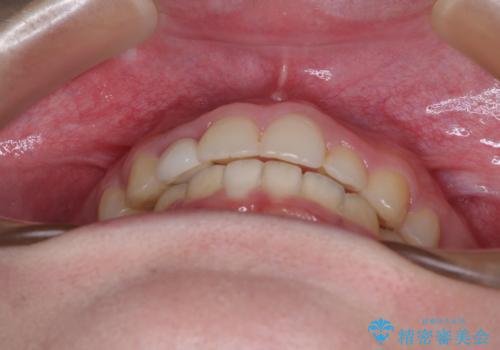

- 前歯の歯並びと不自然な色をした前歯のクラウンを気にして来院された患者様です。

上下前歯の歯列不正はインビザラインにより歯列を整え、その後に、前歯をオーダーメイドタイプのオールセラミッククラウンにて補綴治療することとしました。

前歯のデコボコを一番気にしていらっしゃいましたが、矯正治療により下顎前歯が隠れるほどのディープバイトも一緒に改善され、奥歯に負担のかかりにくい咬み合わせとなりました。